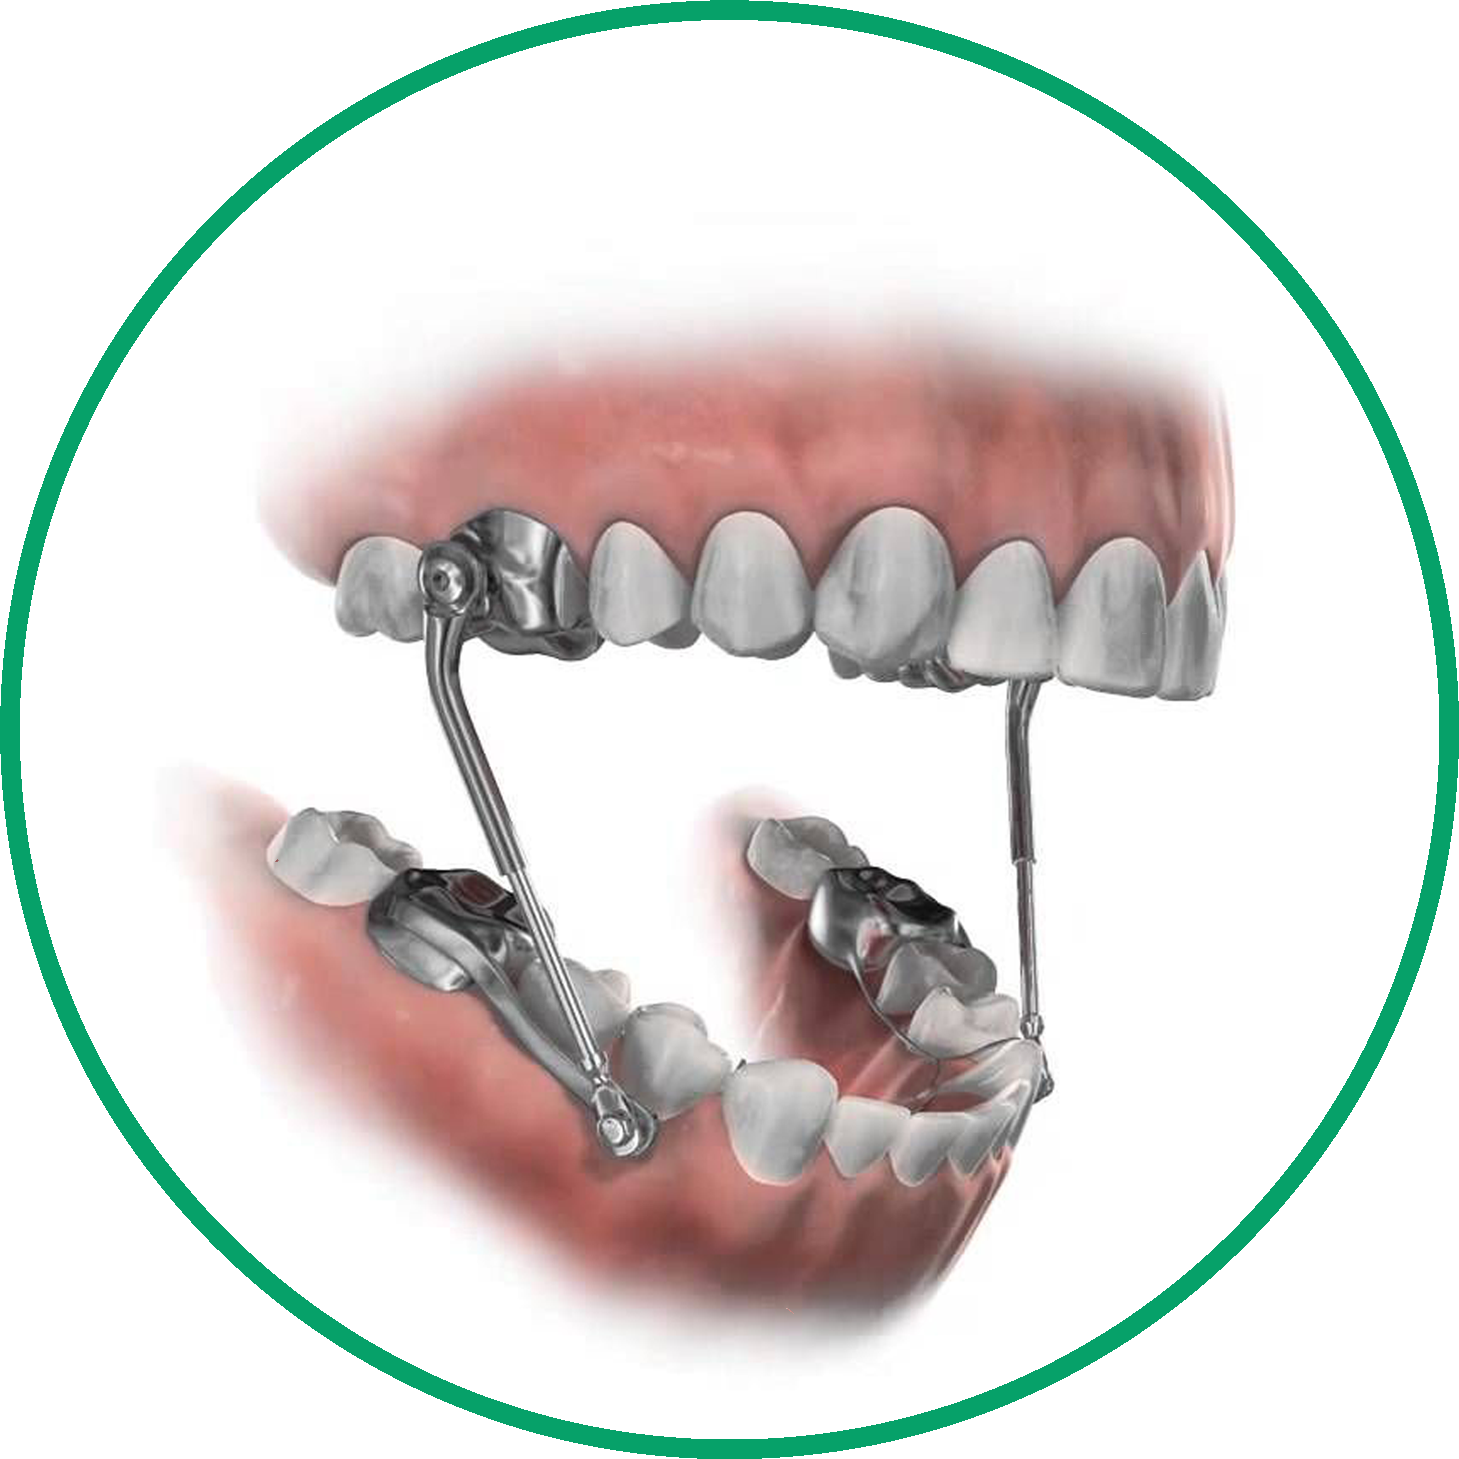

Además de los aparatos metálicos tradicionales, ofrecemos una variedad de opciones de ortodoncia, incluyendo alineadores transparentes, aparatos linguales y aparatos de cerámica, para dar cabida a las diversas necesidades y preferencias de nuestros pacientes.

Los aparatos más comunes son los brackets metálicos o cerámicos, los alineadores transparentes, los aparatos para la cabeza, los retenedores, los aparatos de expansión y los aparatos funcionales. El tipo utilizado depende de cada caso.